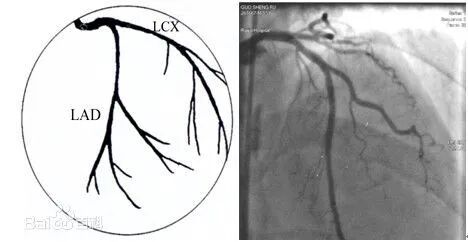

➤左冠状动脉主干(LM)起源于升主动脉左后方的左冠窦,行至前室间沟时分为左前降支(LAD)和左回旋支(LCX)。

✓前降支通常供应部分左室、右室前壁及室间隔前2/3的血液,其分支分别向三个方向发出,即对角支(D)、右室前支、室间隔支。